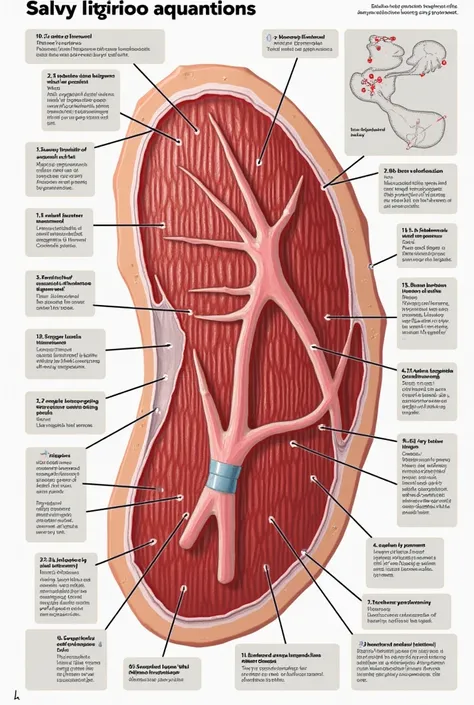

A diagram of the anatomy of the human body

Realice un dibujo de la piel. Coloque las siguientes referencias: Epidermis Fermis Hypodermis Keratinized squamous stratified epithelium Hair Sebaceous gland Sweat gland Pilo erector muscle Connective tissue Blood vessels Nerves Adipocytes

Epidermis Fermis Hypodermis Keratinized squamous stratified epithelium Hair Sebaceous gland Sweat gland Pilo erector muscle Connective tissue Blood vessels Nerves Adipocytes